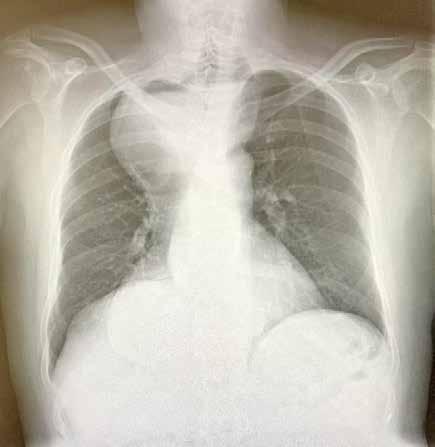

Se revisaron las pruebas solicitadas en Urgencias. En la analítica se en contró una hemoglobina (Hb) de 14 g/dl, un volumen corpuscular medio (VCM) elevado (106μ³) compatible con su historia de alcoholismo o con un déficit de ácido fólico o vitamina B12, una discreta elevación de la proteina C reactiva (13,2 mg/dl) sin elevación de otros reactantes de fase aguda y unas enzimas hepáticas dentro de la normalidad, con la aspartato transfe rasa ligeramente elevada 39 U/L (rango de normalidad: 5-34). Los tóxicos en orina fueron negativos, así como la etanolemia. La radiografía (rx) de tórax mostraba una condensación en el lóbulo superior izquierdo en posi ble relación con la infección tuberculosa diagnosticada en 2011 (Figura 1). La TC -a pesar de no mostrar signos de patología aguda intracraneal, ni masas ni signos de sangrado- sí que mostraba atrofia cerebral con surcos muy marcados, hallazgo no concordante con la edad de nuestro paciente (Imagen 2).

Figura 1. Radiografía de tórax en bipedestación AP y Lat.

Lesiones residuales/cicatriciales en campo superior izquierda, con aumento de densidad de parénquima, bronquictasias y pérdida de volumen, en relación con antecedente de TBC. Parénquima pulmonar derecho aceptablemente ventilado. Siluesta cardiovascular normal.